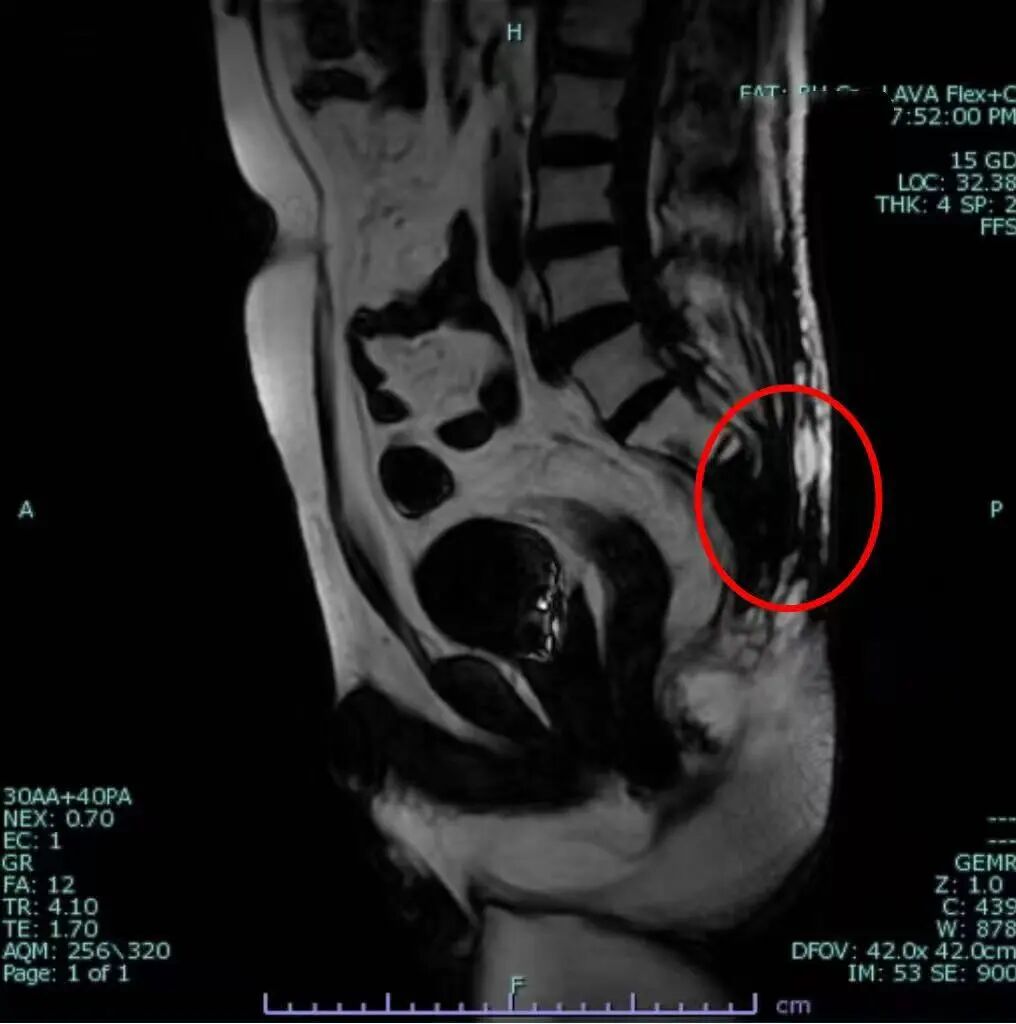

圖片

2024-8初診盆腔核磁:骶尾骨及周圍臀部軟組織彌漫異常信號(hào),考慮腫瘤合并感染形成

該患者罹患骶尾部鱗癌,腫瘤嚴(yán)重侵蝕骶骨,并造成局部皮膚破潰合并感染,導(dǎo)致患者只能長(zhǎng)期被動(dòng)俯臥在床,身心承受著難以想象的巨大痛苦。日夜不休的劇痛和高熱幾乎耗盡了患者的全部生機(jī),生活完全無法自理。為求得一線希望,家屬曾帶著患者奔波于北京多家知名醫(yī)院,嘗試了多種治療方法,但病情始終未見好轉(zhuǎn),希望日漸渺茫。